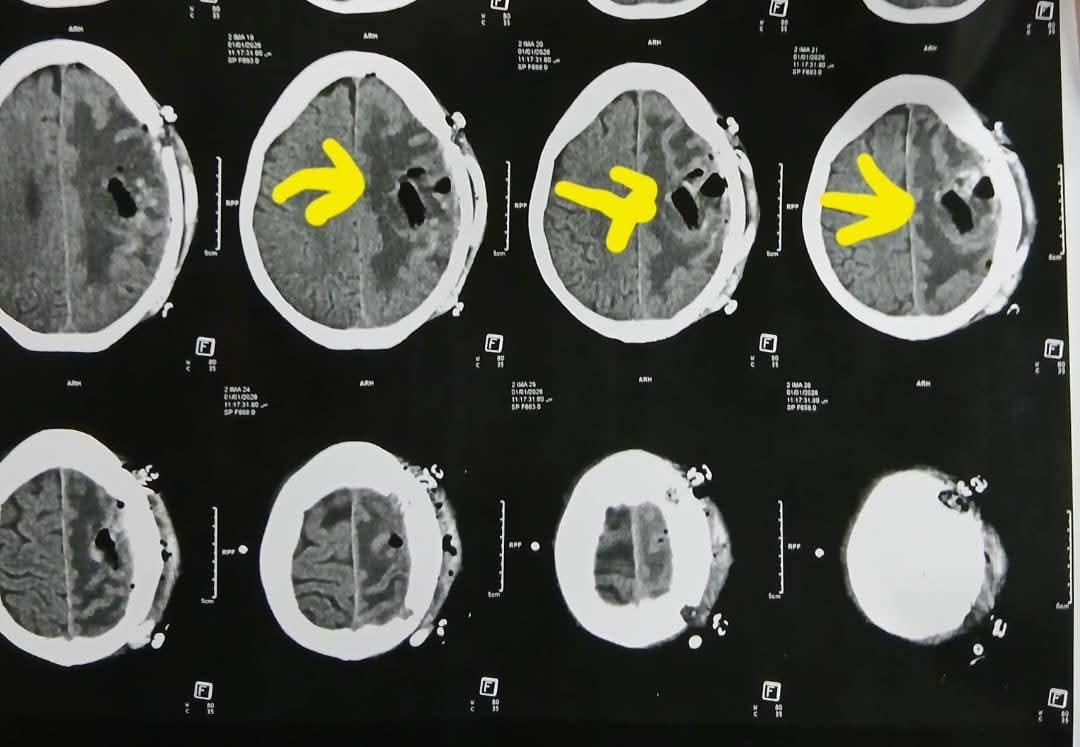

تعود تفاصيل الحالة إلى استقبال المستشفى المريضة بالعيادة الخارجية وهي تشكو من تنميل وضعف بالجانب الأيمن وثقل بسيط في الكلام، وبإجراء الفحوصات اللازمة من أشعة مقطعية ورنين مغناطيسي بالصبغة، تبين وجود ورم بالمخ، وتم إعطاؤها العلاج المناسب لحين استكمال الفحوصات.

ودخلت المريضة غرفة العمليات، حيث أُجريت جراحة مخ دقيقة شملت فتح عظام الجمجمة، وفصل الورم تدريجيًا عن أنسجة المخ مع السيطرة على الأوعية الدموية المغذية له.